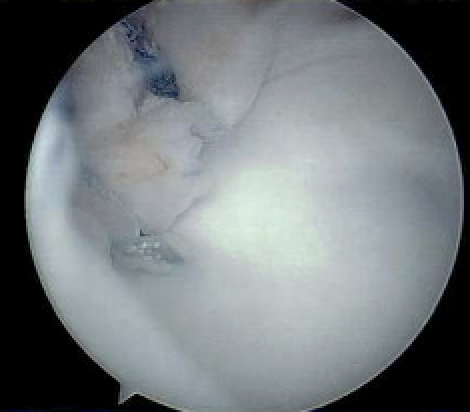

Arthroscopic capsular plication

Technique

Vumedi athroscopic anterior capsular plication

Arthroscopic technique pancapsular shift PDF

Anterior capsular plication +/- rotator interval closure

- option 1: Suture plicate capsule to labrum

- option 2: Anchors in glenoid and use to plicate capsule to labrum

Anterior capsular plication with sutures

Anterior capsular plication with suture anchors

Posterior capsular plication

Posterior capsular plication with suture anchors